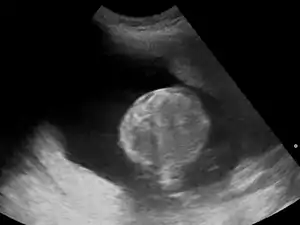

اگر پزشک به پلی هیدرآمنیوس مشکوک باشد ابتدا یک سونوگرافی از جنین انجام میدهد. او با اندازهگیری بزرگترین و عمیقترین پاکه اطراف جنین، حجم مایع آمنیوتیک (AFV) را تخمین میزند. اگر مقدار AFV از ۸۰۰ میلیمتر بیشتر بود به معنی ایجاد پلی هیدرآمنیوس میباشد.

گاهی وقتها نیز برای اندازهگیری میزان مایع آمنیوتیک مقدار آن را در چهار قسمت از رحم شما که بیشترین عمق مایع را دارد اندازه میگیرند. به مجموع این اندازهگیریها شاخص مایع آمنیوتیک (AFI) گفته میشود که اگر بیشتر از ۲۵ سانتیمتر شود به معنی وجود پلی هیدرآمنیوس است.[4]